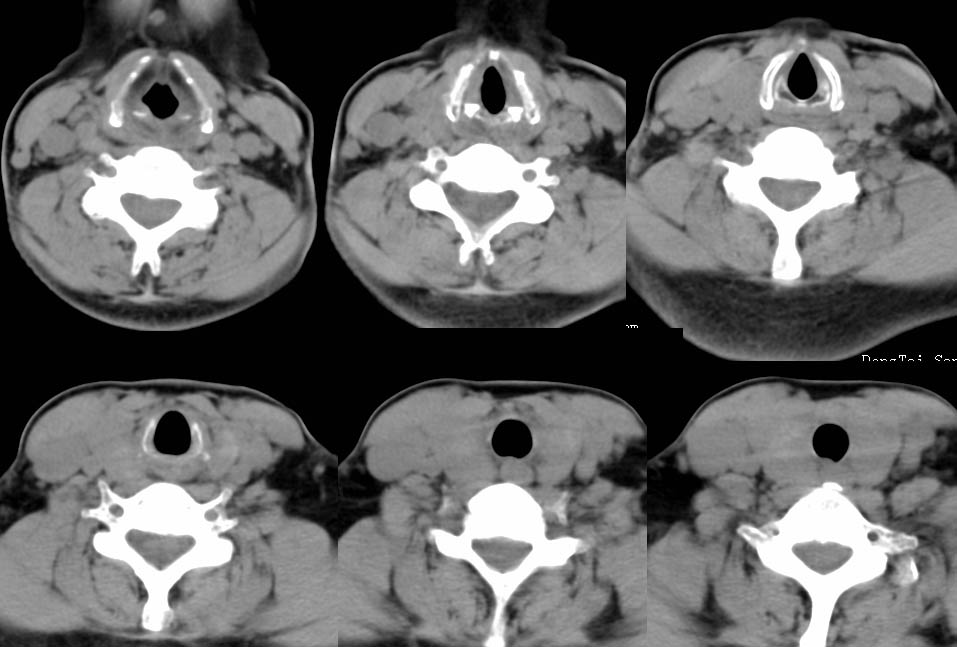

以下是引用zhangzhongshou在2007-4-23 12:41:00的发言:[br]甲状腺弥漫性肿大,密度减低,符合甲状腺炎ct表现,建议进一步检查